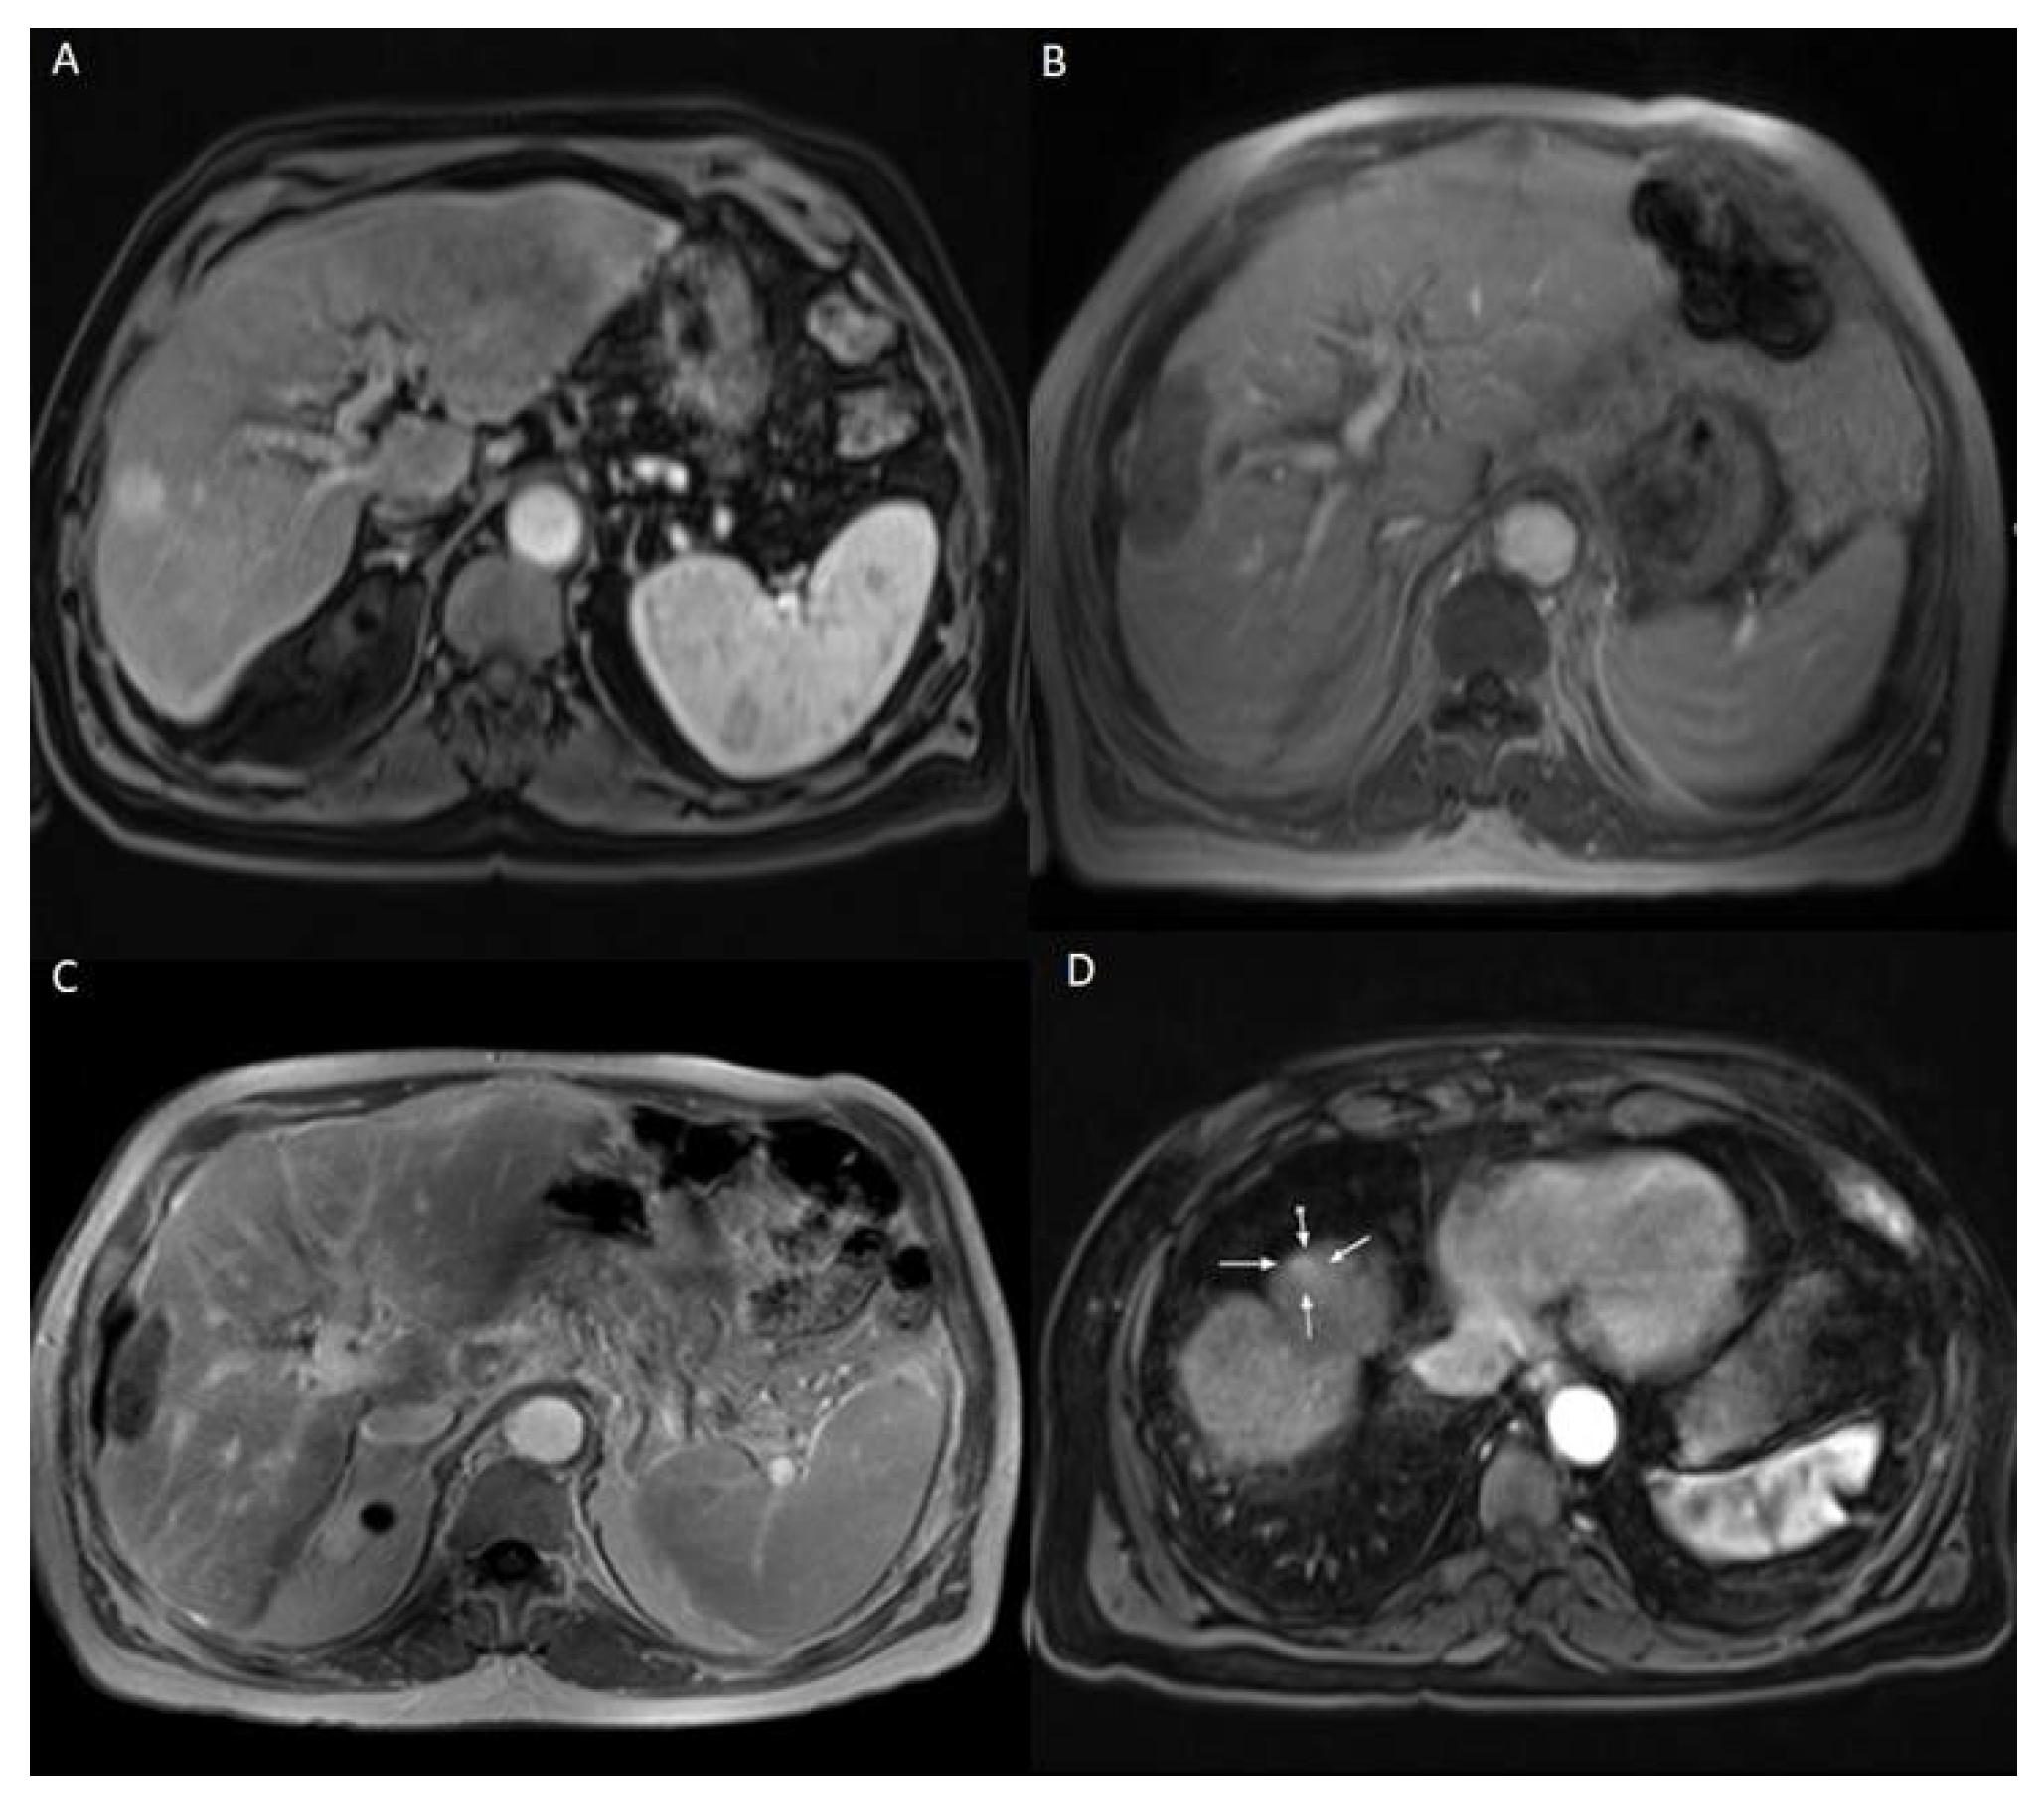

The patients who developed LTP or IDR were treated by MWA, LITT, or TACE, depending on the number, size, and location of the new HCC lesions. The decision was taken by the multidisciplinary tumor board. Examples of Patients’ cases are shown in Figure 1 and Figure 2.

Figure 2. 69 years old male patient with chronic hepatitis C virus, liver cirrhosis, and HCC lesion in the right liver lobe, who was treated with LITT. (A) Pre-treatment CEMRI showed an arterial hyperenhancement of the lesion. (B) 24 h post-ablation CEMRI showed a large post-ablation zone, and the lesion was fully ablated. (C,D) At the 3-months post-ablation CEMRI, the size of the ablation zone was getting decreased without LTP, but there was a hyperenhancement in untreated liver segment (white arrows), which was correlated with IDR. TACE was performed to treat the recurrent HCC and the patient lived for 33 months after LITT until death.